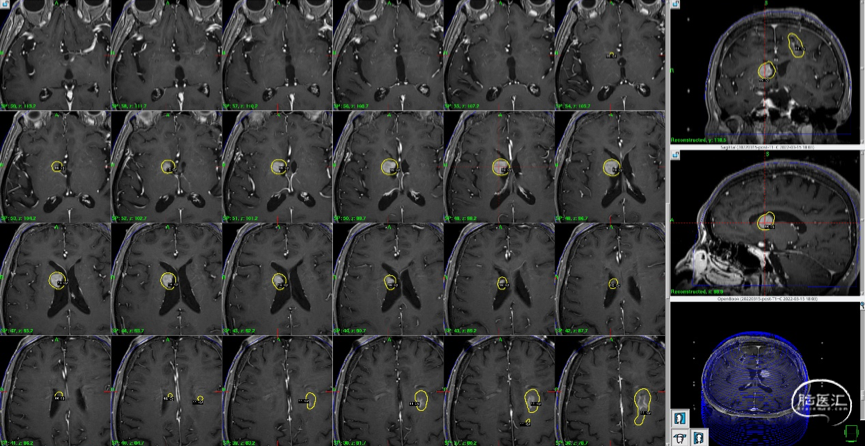

2)右侧侧脑室壁病灶体积缩小显著:

再次伽玛刀治疗

影像随访:

1)左额病灶:囊性病变逐渐缩小

6个月随访时,薄扫增强磁共振(1mm/层)提示肿瘤明显缩小,无放射相关不良反应,没有新发病灶;患者目前仍在规律的随访当中,期待我们的长期随访结果。